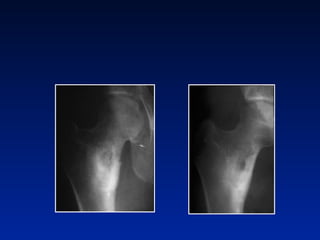

OSTEOMA  OSTEOIDE Formas juxta-articulares

Tratamento cirurgico exerese de nicho Nicho em colo femural

Tratamento cirúrgico Mulher 19 anos